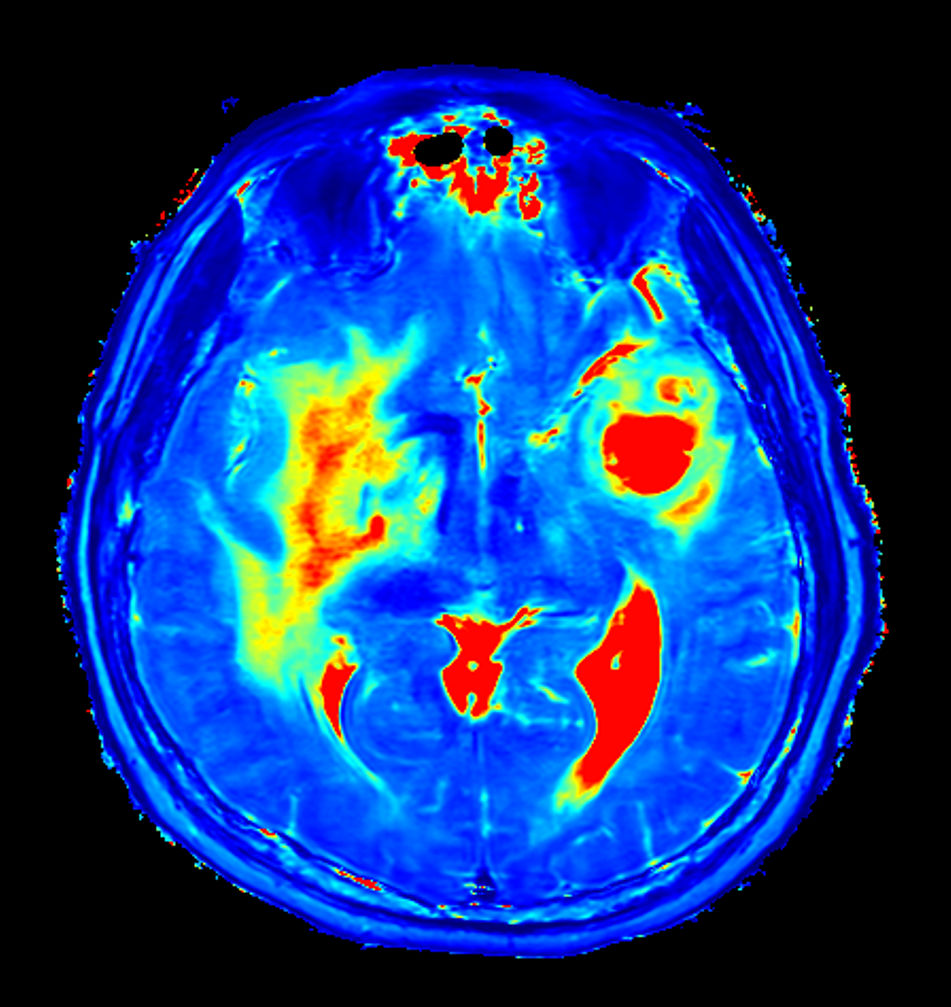

Axial 3D pCASL (3 dynamics)

Axial 3D APT